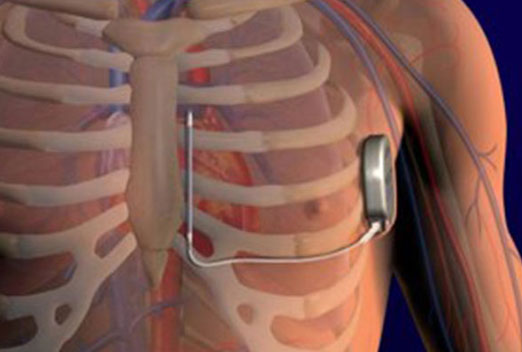

We have a some latest projects photos and Videos. this gallery explain different

health issues related to heart and more information for heart patients thats ill we help for your health improve.